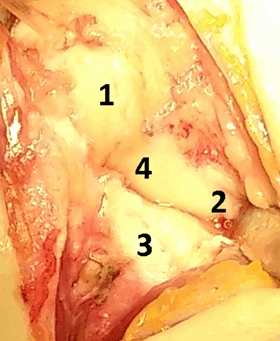

Описание техники оперативного лечения. Операция проводилась под региональным обескровливанием при помощи пневматического жгута. В положении пациентки на спине рука располагалась на приставном столике. Выполнялся тыльный продольный доступ в проекции лучезапястного сустава. Остро и тупо препарировались мягкие ткани с визуализацией сухожилий разгибателей пальцев кисти. Удерживатель сухожилий разгибателей рассекался в третьем компартменте, после чего сухожилия разгибателей пальцев кисти разводились в разные стороны. Капсула сустава рассекалась Т-образно. В полости лучезапястного сустава визуализировалось избыточное содержание синовиальной жидкости, разрастание синовиальной оболочки сустава, отрыв ладьевидно-полулунной связки (рис. 3). При ревизии трехгранного комплекса патологических изменений выявлено не было. Осуществлялось проведение биодеградируемого пина 1,5 мм через ладьевидно-полулунное сочленение по оси полулунной кости для сопоставления костей проксимального ряда запястья. Контроль положения ладьевидной и полулунной костей был исследован при помощи электронно-оптического преобразователя (далее ЭОП). В область дефекта ладьевидно –полулунной связки в проксимальный полюс ладьевидной кости устанавливался биодеградируемый якорный фиксатор с последующим восстановлением целостности поврежденной тыльной порции ладьевидно-полулунной связки (рис. 4). Восстановление осуществлялось за счет формирования дубликатуры культи связки и её трансоссальной фиксации к полулунной кости. В дальнейшем осуществлялась пластика капсулы лучезапястного сустава. Восстанавливалось положение сухожилий разгибателей пальцев правой кисти, осуществлялась пластика удерживателя сухожилий.

На фотографии (рис. 4) во время операции видна восстановленная ладьевидно-полулунная связка. Послойно накладывались швы на рану, асептическая повязка, гипсовая иммобилизация лучезапястного сустава.

Рис. 4. Реинсерция ладьевидно-полулунной связки: 1 – ладьевидная кость, 2 – полулунная кость, 3 – лучевая кость, 4 – полулунно-ладьевидная связка